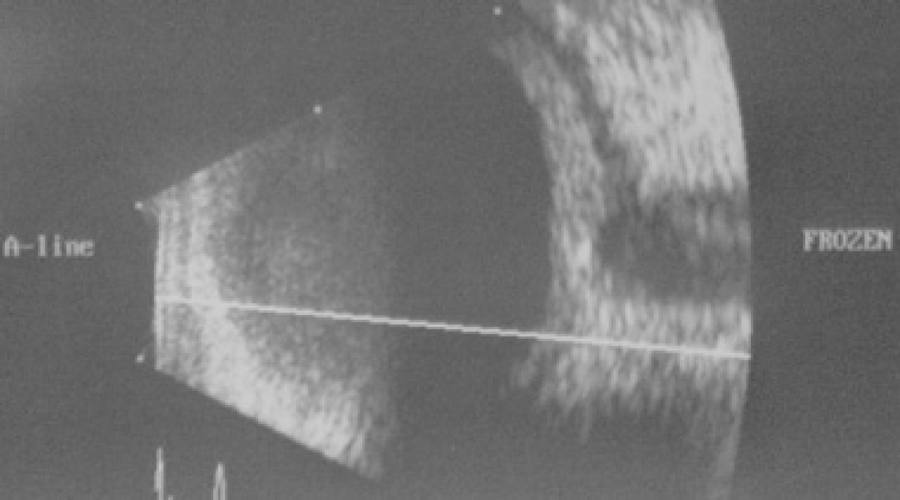

Macular optical coherence tomography (OCT) showed edema with neurosensory retinal detachment in the left eye. B-scan ultrasonography (Figure 2) revealed sclerochoroidal thickening and the presence of sub-Tenon's space fluid (T-sign).

Some authors have suggested that infection due to TB should be considered as a possible cause of scleritis if the investigation reveals a positive PPD skin test, particularly if the scleral inflammation does not respond adequately to standard corticosteroid treatment(5). Given the worsening of the optic disc edema, no improvement of the BCVA, orbital CT scan, and B-scan ultrasonography with oral corticosteroids, and the positive results from the PPD skin and IGRA tests, we assumed that TB was the causative agent of the posterior scleritis, and started antitubercular therapy. An intraocular sample to confirm the diagnosis of Mycobacterium tuberculosis infection was not performed as the patient responded well to the combined treatment of oral corticosteroids and antitubercular therapy. In our investigation, we could not establish the presence of any connective tissue disorder in our patient, and she has had no recurrences in the 18 months of follow-up, which suggests a non-connective tissue disorder as an etiology. Some authors consider a therapeutic trial to be justified in patients with severe sight-threatening intraocular inflammation and latent TB infection(6). Furthermore, the addition of antitubercular therapy to corticosteroids in uveitis patients with latent/manifested TB has been shown to reduce the recurrences of uveitis(7).